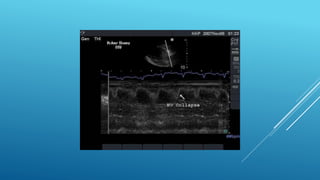

Phases of Hemodynamic changes in Tamponade,

Phases of Hemodynamicchanges in Tamponade, Phase I With Accumulation of pericardial fluid Impairs Relaxation and Filling of Ventricles, Requiring Higher Filling Pressure; during this phase, LV & RV Filling Pressures are Higher than IntraPericardial Pressure Phase II With further Fluid Accumulation, Pericardial Pressure increases Above Ventricular Filling Pressure, Resulting in Reduced Cardiac Output Phase III With further Decrease in Cardiac Output , which is due to Equilibration of :;: Pericardial and (LV) Filling pressures